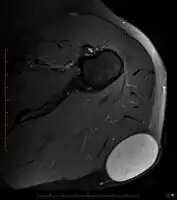

In terms of the diagnosis of a sebaceous cyst an MRI (Magnetic resonance image) may be used